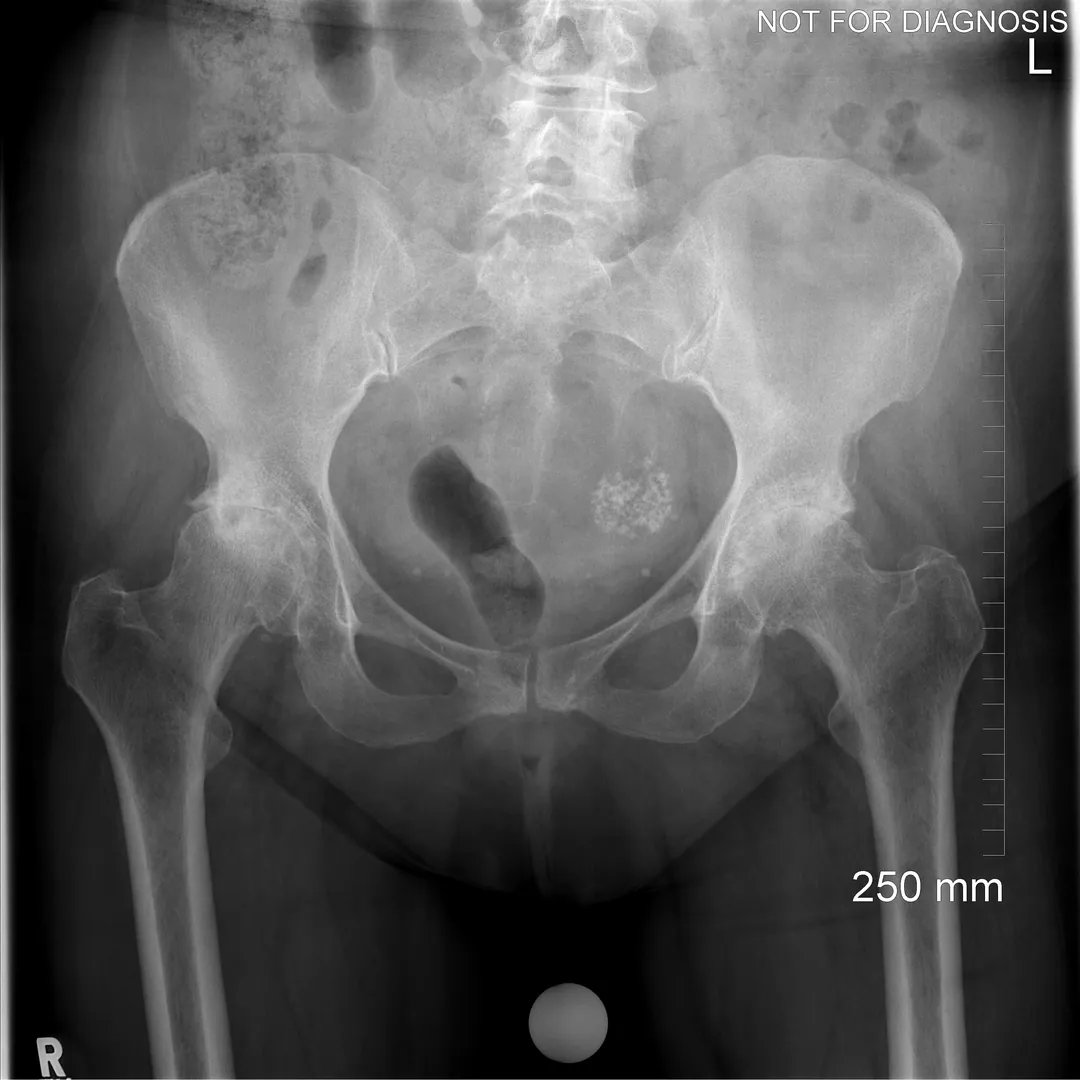

A total hip replacement (also called total hip arthroplasty) is a surgical procedure in which a damaged or worn hip joint is replaced with artificial components. The hip is a ball-and-socket joint, meaning the ball at the top of the thigh bone sits in a socket on the pelvis. During surgery, the damaged ball (femoral head) is replaced with a metal or ceramic ball attached to a stem, and the damaged socket is replaced with a metal cup lined with plastic, ceramic, or metal.

Hip damage caused by conditions such as:

- Osteoarthritis (most common)

- Rheumatoid arthritis

- Avascular necrosis (loss of blood supply to the hip bone)

- Hip fracture or trauma

- Congenital or developmental hip disorders

Osteoarthritis (most common)

Rheumatoid arthritis

Avascular necrosis (loss of blood supply to the hip bone)

Hip fracture or trauma

Congenital or developmental hip disorders